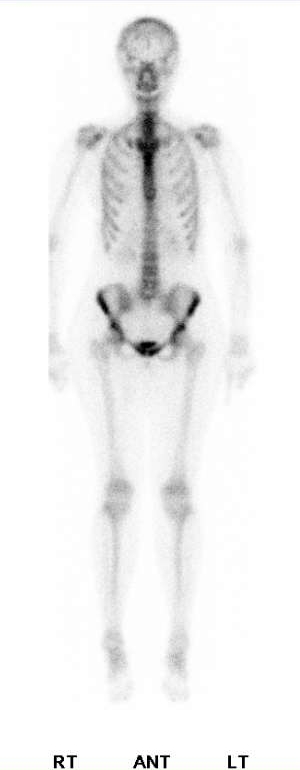

★到底是不是假影?

這是一位30多歲的肺癌女性患者,在連續的bone scan追蹤系列影像,由於是肺癌患者,所以大家的焦點都集中在肺部,可是在中間的那一次檢查裡,我們的醫生突然發現病人右邊的股骨頸那邊好像出現了甜甜圈的影像,該不會是治療的藥物造成了那邊的缺血性壞死AVN?於是就在報告上提到了這件事,然後臨床的醫師也很關心這個情形,就安排了核磁共振,結果卻是正常,接著病人又來進行第3次的bone scan追蹤,這次原先懷疑是AVN的地方竟然就沒事了,我跟我們家的醫師反反覆覆的看了幾次影像的原始檔,最後得出的結論是,第2次的影像有可能是口袋裡有銅板,造成的影像缺損才會那麼的圓,但是由於當時也沒有補局部的影像,因此一切也都是猜測。這件事告訴我們,首先,就算是已經確定病情的患者,在判讀影像時也要多留意其他的區域,才不至於有遺漏的地方,再者,就算病人說身上都沒有金屬或是其他異物,也不代表你可以放心的照,看到怪怪的地方,還是多檢查一遍會比較好。

2018/7/23 |

2018/10/19 |

2019/1/14 |